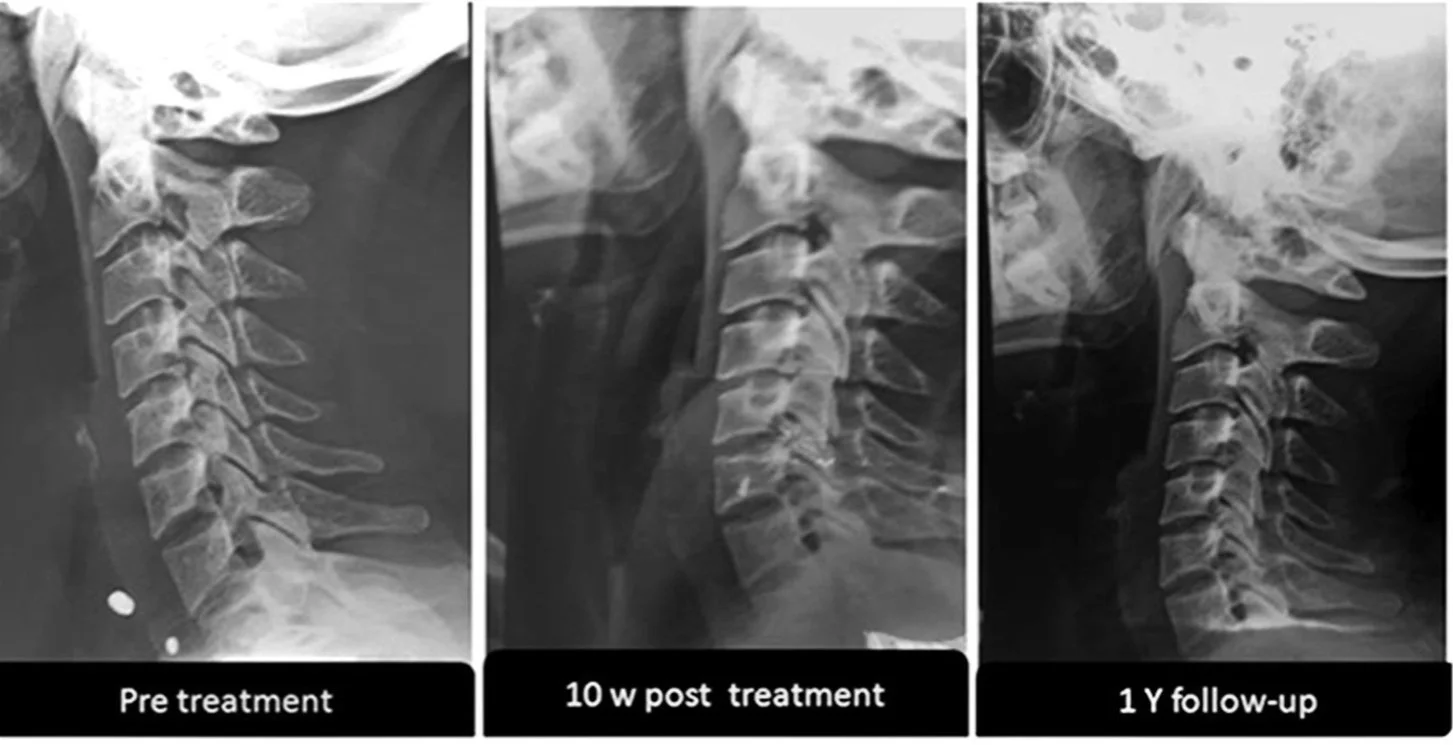

• Evaluated at baseline, 10 weeks, and 1 year

• At 10 weeks:

• Both groups had similar arm pain, neck pain, and DSSEP latency improvements.

• Intervention group had significantly better outcomes in:

• Cervical lordosis and AHT

• At 1-year follow-up:

• Control group reverted toward baseline.

• Intervention group maintained significant improvements in all measured variables: